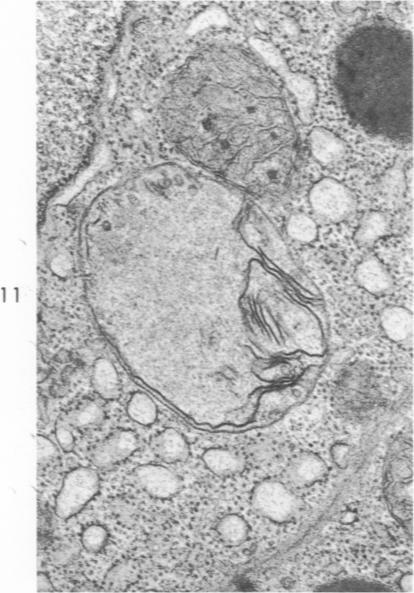

Early changes in the exocrine pancreas of the dog and rat after ligation of the pancreatic duct. A light and electron microscopic study.

Am J Pathol. 1971 Jun;63(3):521-46.